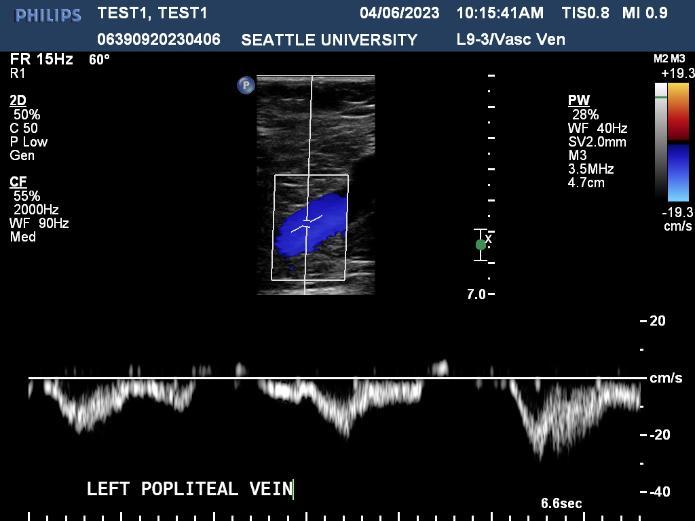

Ultrasound is a non-invasive diagnostic tool that uses high-frequency sound waves to propagate images of organs and tissues within the body. The Diagnostic Ultrasound program at Seattle University offers three distinctive track specializations in General (abdomen extended, OB/GYN) Vascular and Cardiac sonography.